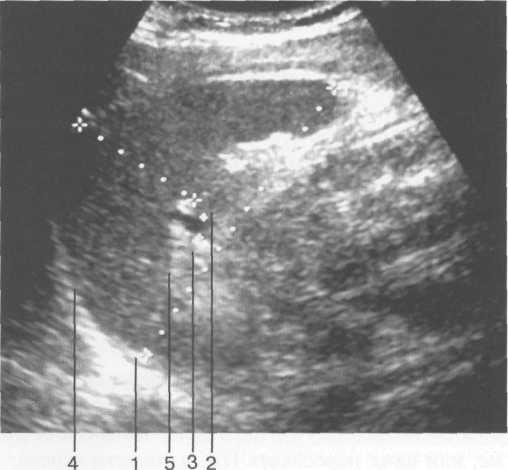

УЛЬТРАЗВУКОВАЯ АНАТОМИЯ СЕЛЕЗЕНКИ

При ультразвуковом исследовании для оценки размеров селезенки используют измерение ее длины (расстояние между передним и задним концами), ширины (расстояние между верхним и нижним краями) и толщины (расстояние между наружной и внутренней поверхностями на уровне ворот). Сведения о средних размерах селезенки в зависимости от возраста представлены в табл. 11.4.

Рис. 11.23. УЗИ селезенки, продольное сканирование.

1 — длина селезенки; 2 — толщина селезенки; 3 — селезеночная вена в воротах селезенки; 4 — верхняя (диафрагмальная) поверхность; 5 — нижняя поверхность.

Для изучения размеров селезенки (в том числе в динамике) предложено определять селезеночный индекс, величина которого является произведением расстояния от ворот селезенки до ее переднего полюса и толщины органа на уровне ворот. В норме селезеночный индекс не превышает 20 см 2 .

Селезеночная вена в норме визуализируется в виде анэхогенной полосы, диаметр ее не зависит от возраста, но обычно не превышает 7 мм.

Паренхима селезенки имеет однородную мелкозернистую структуру, обладает эхогенностью ниже печени, но несколько выше чем у коркового вещества почки. Капсула селезенки представлена в виде линейного гиперэхогенного слоя, интенсивность которого увеличивается с возрастом за счет склерозирования, что особенно заметно у пациентов старше 60 лет (рис. 11.23).